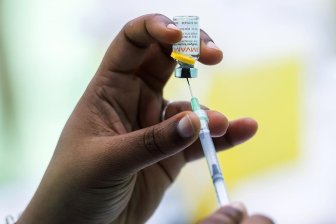

Alberta expands eligibility of monkeypox vaccineThe Alberta government is expanding the eligibility criteria of the monkeypox vaccine to those at high risk for exposure to the virus.HealthJul 28, 2022

Monkeypox: Canada’s top doctor urges those at risk to get vaccinated as cases climbMonkeypox, which causes flu-like symptoms and skin lesions, is transmitted to humans from animals caused by an orthopoxvirus, which is related to smallpox, according to PHAC.CanadaJul 27, 2022

Quebec now has 211 confirmed cases of monkeypox as vaccination numbers riseThe Health Department's latest update shows that 8,101 doses of smallpox vaccine Imvamune have been administered across Quebec since May 27.CanadaJun 30, 2022

Quebec tops 200 confirmed cases of monkeypoxAlong with the latest monkeypox numbers, Quebec's health department reported that 7,568 doses of smallpox vaccine Imvamune have been administered in the province since late May.CanadaJun 28, 2022

Quebec now has 90 confirmed monkeypox casesThe latest update from the province's health ministry also shows that 813 doses of the vaccine against the virus have been administered to date.CanadaJun 7, 2022